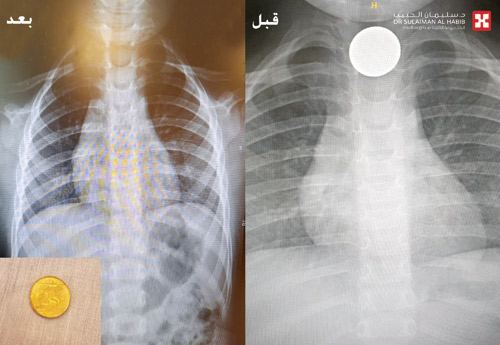

وقال الدكتور نظير إن نتائج الفحوصات أثبتت وجود عملة معدنية في الثلث العلوي من المريء، وهي المتسببة في أعراض الاختناق التي أصابت الطفل، وتقرر بعد دراسة الحالة إجراء عملية عاجلة باستخدام تقنيات المنظار المتطور، مشيراً إلى أن العملية استغرقت نصف ساعة تحت التخدير العام، وتم فيها الدخول بمنظار خاص لمثل هذه الحالات وإزالة القطعة المعدنية.

وأفاد الدكتور نظير بأن جهود الفريق الطبي تكللت بالنجاح وإنقاذ الطفل ولله الحمد، وبمرور ساعتين استفاق وبدأ في اللعب والحركة وأصبح يتنفس بصورة طبيعية، ولمزيد من الاطمئنان تم إجراء أشعة على منطقة الصدر والتي أكدت نجاح العملية، كما استطاع الطفل تناول الطعام بشكل طبيعي، وخرج إلى منزله في نفس اليوم وهو في حالة جيدة وطبيعية.